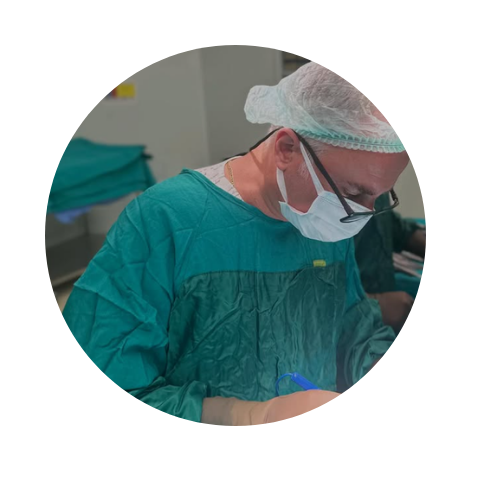

DOÇ. DR. SÜLEYMAN BULUT

Üroloji Doktoru

2002 — Ankara Numune Eğitim ve Araştırma Hastanesi, Üroloji Kliniği

1997 — Ankara Üniversitesi Tıp Fakültesi